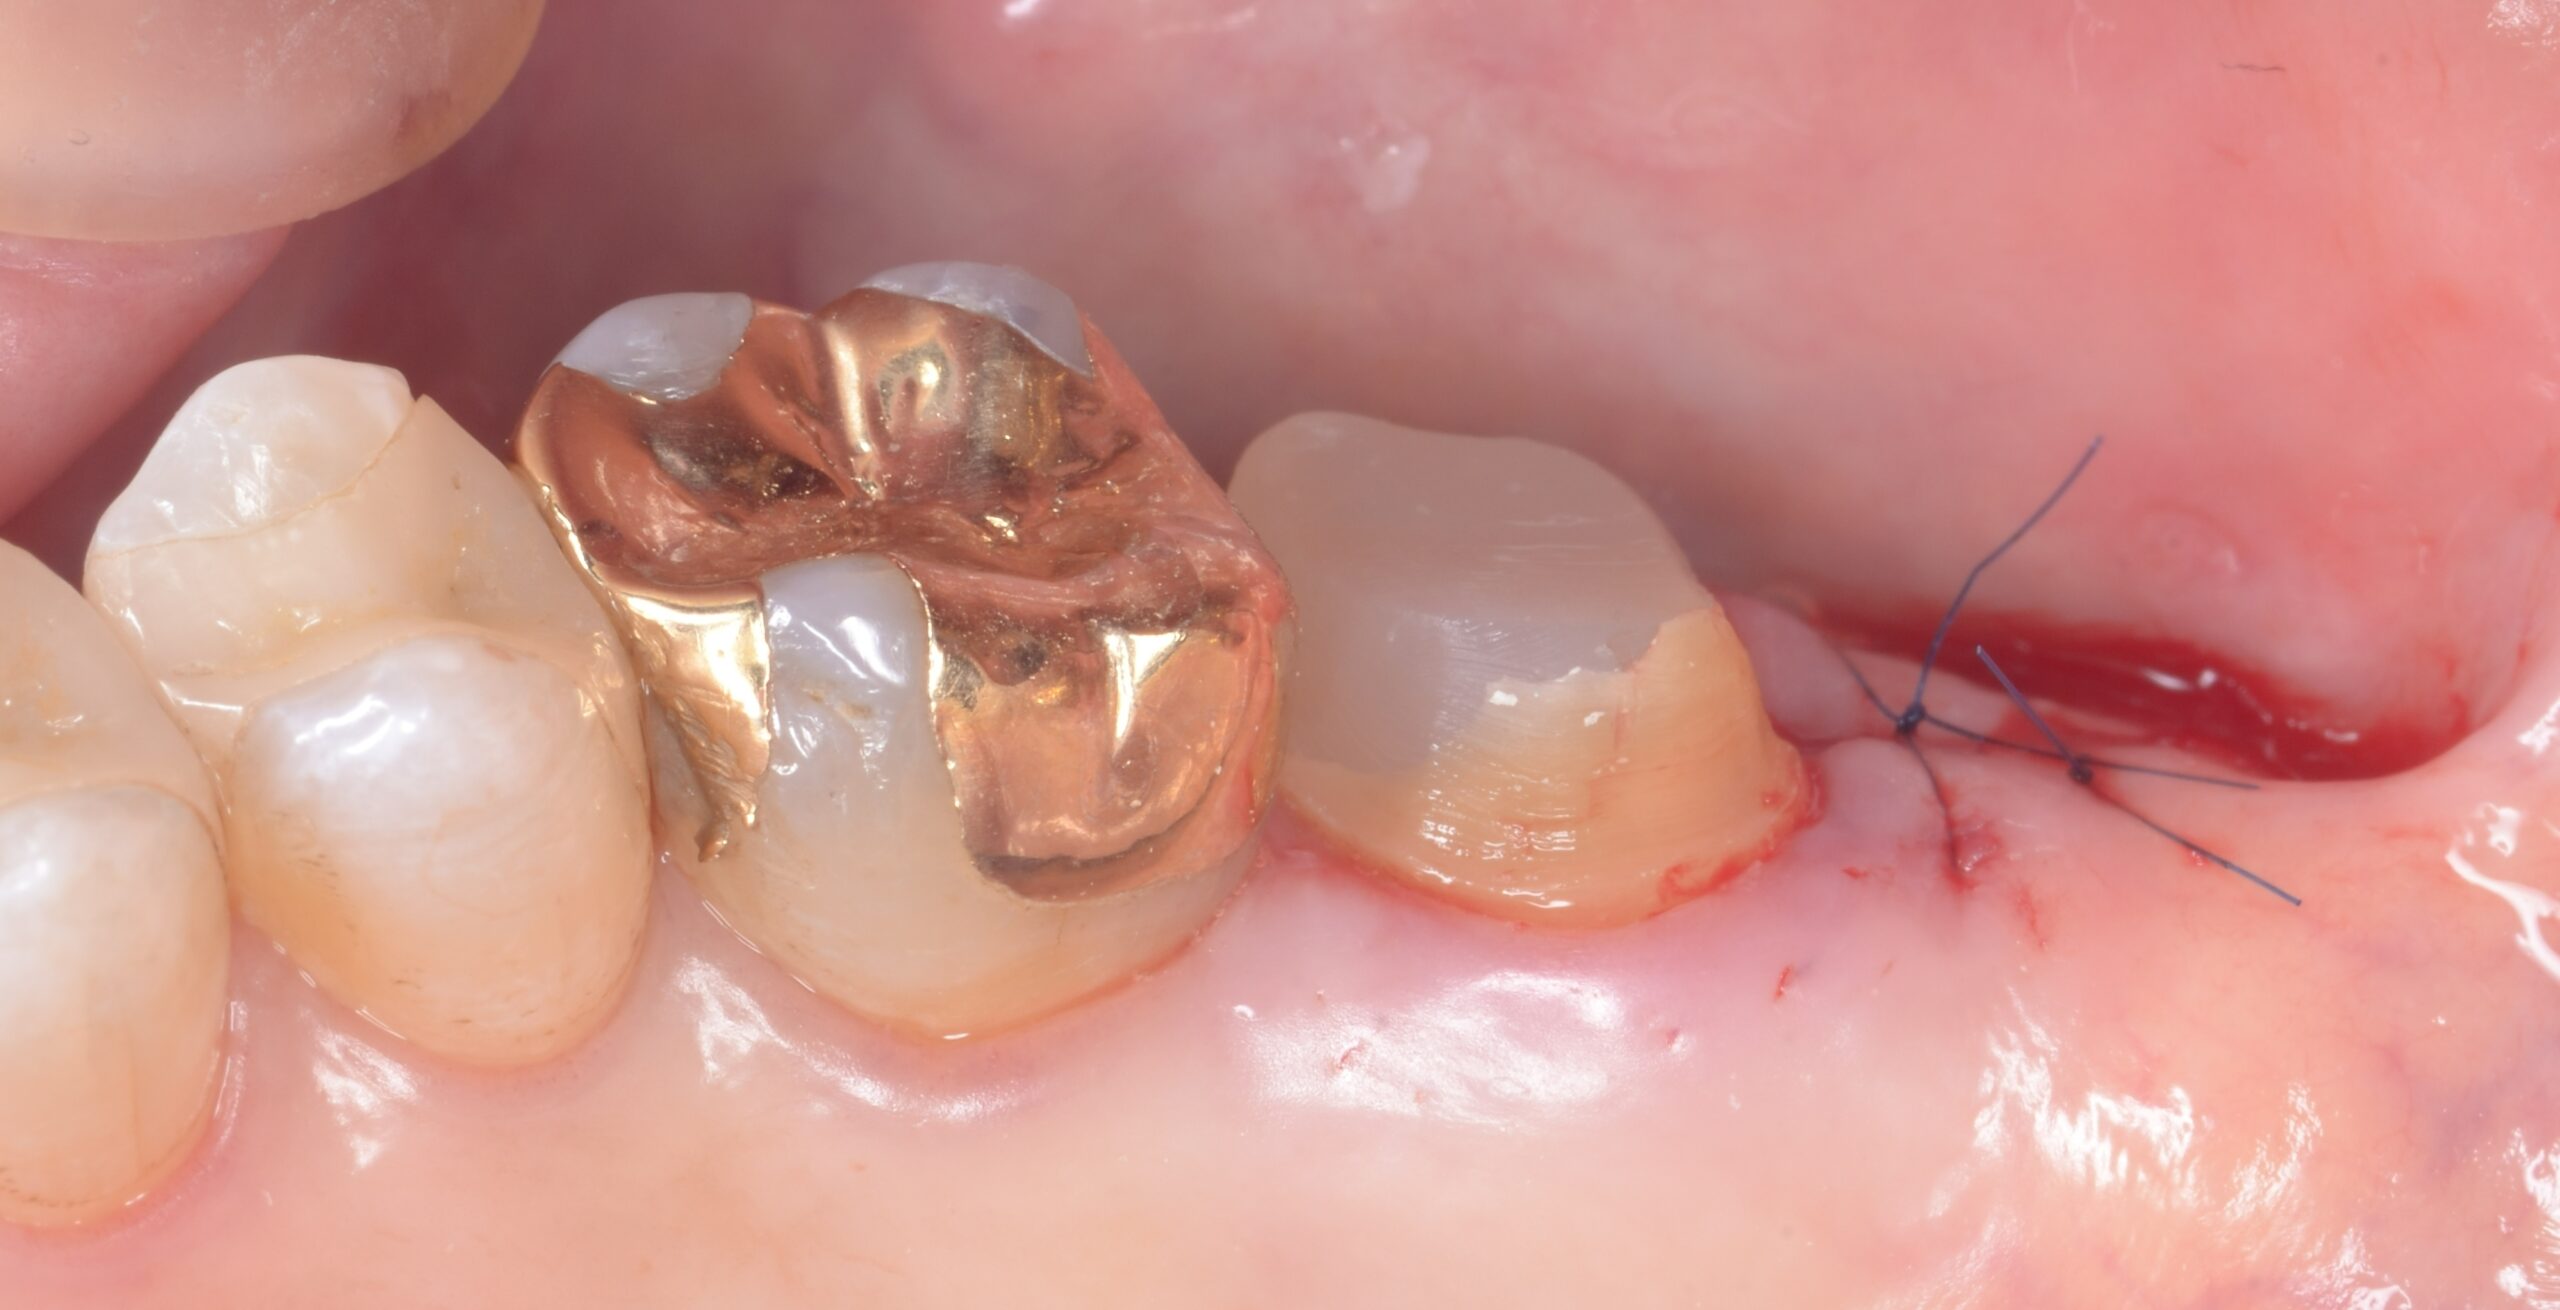

外科処置

歯周基本治療後も右上7遠心部に歯肉の肥厚およびポケット残存が認められたため、ディスタルウェッジ手術を行った。

第二大臼歯遠心部の過剰歯肉を楔状に切除し、歯肉形態を整えることでポケットの減少および清掃性の改善を図った。術後は良好な歯肉形態が獲得され、遠心部のプラークコントロールが容易となった。